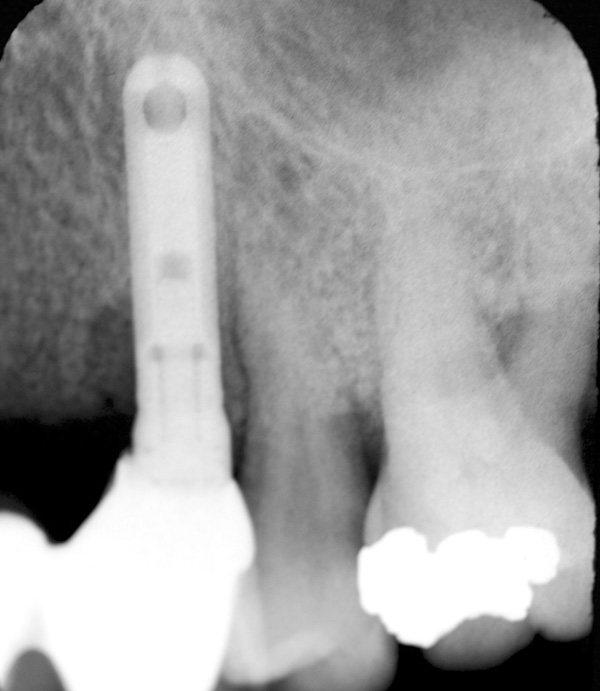

Radiograph evaluation—Radiographs can help determine if a tooth, implant, or sequestering bone are contributing to an infection. In specific situations—for example, various forms of osteomyelitis—infections may affect the appearance of the bone. A non-vital tooth can manifest a radiolucent apical area; sinus infections usually demonstrate a cloudy sinus; and other alterations of bone density or trabecular pattern may be associated with an infection.

Figure 4 Radiograph of site No. 12 manifesting alveolar bone loss that is associated with an infection. (Radiograph courtesy of Dr. John Cavallaro.)

Figure 4